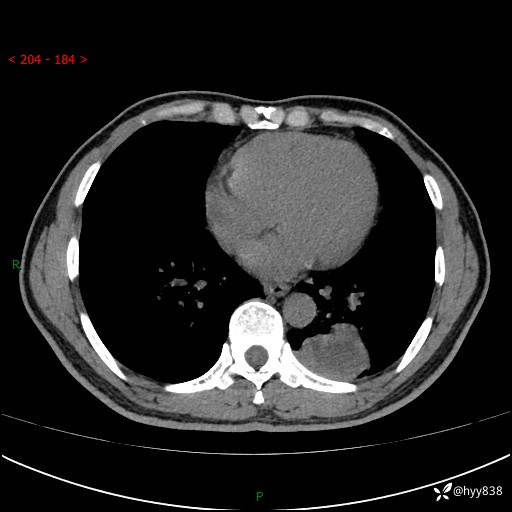

57岁/男,间断痰中带血1月余。纤支镜没有取到东西,穿刺轻松搞定---结果公布~

现病史:患者1月余前无明显诱因出现咯血症状,为痰中带血,量不大,伴轻度咳嗽,2024-3-26于当地市中医医院行胸部CT示:左肺下叶占位性病变。现患者仍有咳嗽不适,无发热乏力,无腹泻、便秘,无咳嗽,无头晕、无双下肢水肿等伴随症状,未行特殊治疗,今日患者再次出现咯血症状。患者为求进一步诊治,遂入我院,门诊以“肺脓肿”收入我科。 患者病程中,精神食欲可,二便正常,体力体重较前变化不明显。

增强

下肺占位,穿刺明确病理